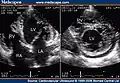

Transthoracic two-dimensional echocardiogram in apical four chamber and parasternal short axis at the level of both ventricles demonstrate dilatation, deep trabeculae and intertrabecular recesses in the inferior, lateral, anterior walls, middle and apical portions of the septum and apex of the left ventricle. [3] -

Two-dimensional parasternal and color Doppler images at the level of both ventricles that show the noncompacted:compacted wall ratio and how the color enters the intertrabecular recesses [4]